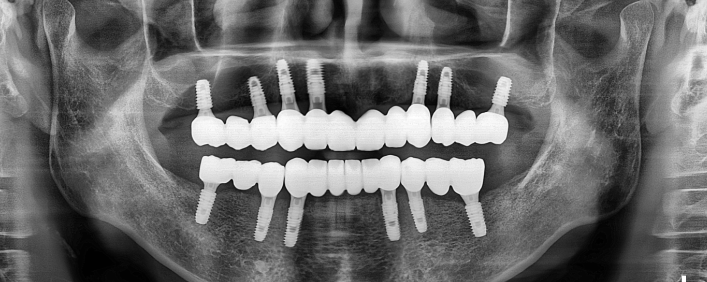

전악 임플란트

치아가 전혀 없거나 소수일 경우, 임플란트를 이용하여 전체 치아를 복원해주는 시술입니다.

자연치아는 위/아래 14개씩 모두 28개가 존재합니다.

자연치아가 상실될 경우, 본래의 치아처럼 회복하기 위해 다수의 임플란트를 식립해야 합니다.

전악 임플란트는 큰 범위의 시술인 만큼 많은 수술 경험으로 기술과 노하우가 필요합니다.

임플란트 치료사례

서울스마트치과는 결과로 증명합니다.

위 치료 사례는 서울스마트치과에서 직접 치료를 받고, 환자 본인의 동의를 얻어 게재된 사진으로 무단 인용, 도용, 재배포 시 민/형사상 책임을 질 수 있습니다.